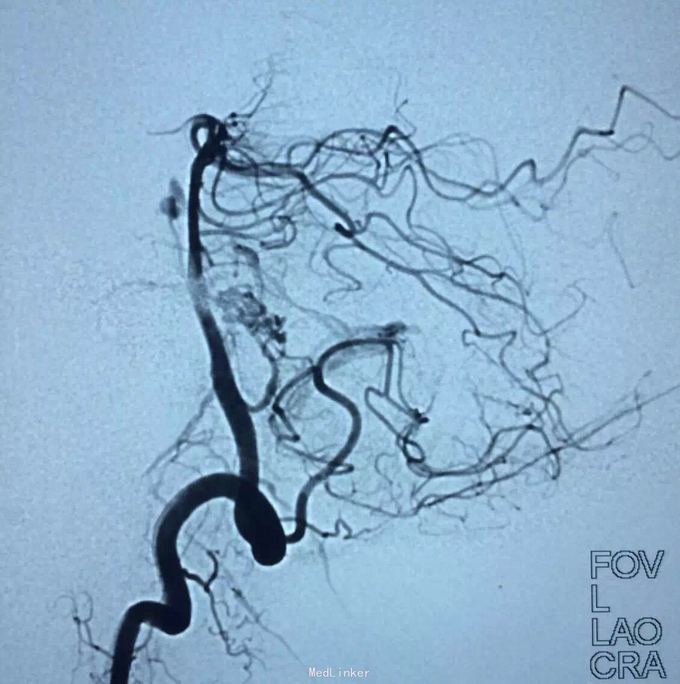

AVM

小脑出血

介入治疗